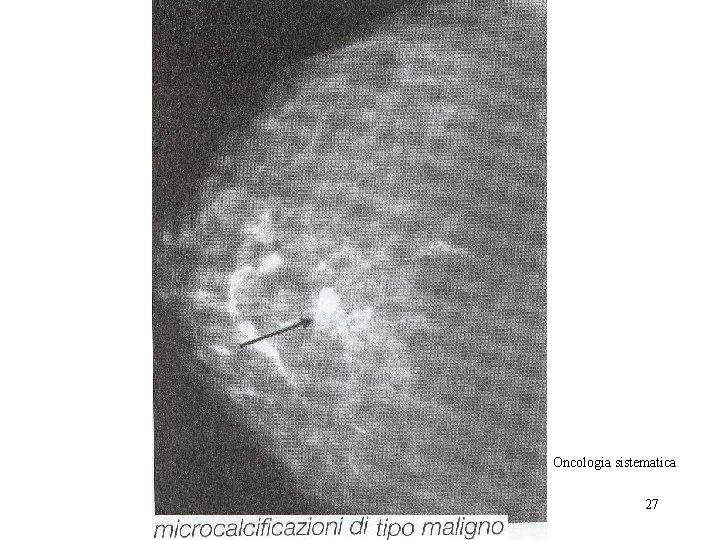

Oncologia sistematica 27